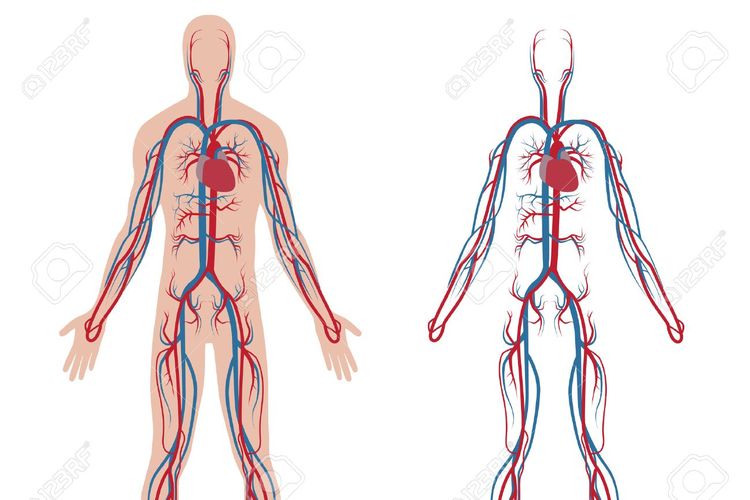

1 mengangkut sari sari makanan oksigen hormon ke seluruh tubuh. Pernyataan berikut adalah fungsi dari sistem sirkulasi atau peredaran darah pada manusia kecuali. Sistem peredaran darah berfungsi untuk mengangkut oksigen dan nutrisi keseluruh tubuh mengangkut sisa metabolisme ke organ ekskresi dan mengatur suhu tubuh.

Sistem peredaran darah besar istemik adalah sistem peredaran darah yang berasal dari jantung dan akan menuju organ organ yang berada di tubuh manusia secara keseluruhan kemudian akan di bawa ke jantung. K13 Revisi Antiremed Kelas 8 Biologi-Sistem Peredaran Darah Latihan Soal doc. Salah satu bagian darah yang memiliki peranan bagi pembekuan darah ialah.

Sistem peredaran darah memiliki 5 fungsi utama. 2 mengangkut sisa metabolisme sel untuk dibuang ke ginjal. Gangguan pada pembuluh nadi yang mengeras yang diakibatkan endapan lemak disebut.